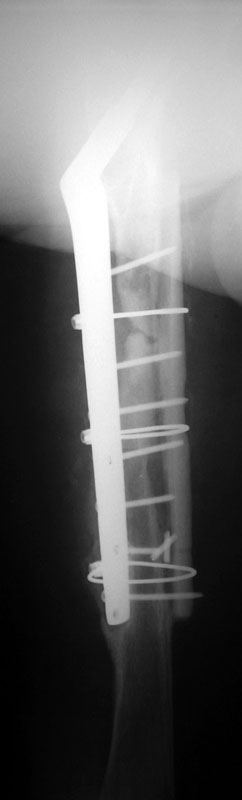

02/02/02 lat

02/08/02 AP

02/08/02 lat